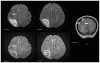

This case report describes how eculizumab reversed neurologic impairment and improved renal damage in severe atypical hemolytic uremic syndrome. A 50-year-old female, after presenting with diarrhea and abdominal pain, developed pancolitis, acute renal failure, and thrombocytopenia. The patient underwent total abdominal colectomy. Pathology confirmed ischemic colitis with scattered mesenteric microthrombi. Due to mental and respiratory decline, she remained intubated. Continuous venovenous hemodialysis was initiated. Renal failure, neurologic changes, hemolysis, thrombotic microangiopathy, and low complement levels all suggested atypical hemolytic uremic syndrome. Eculizumab 900 mg was administered intravenously on hospital day 6 and continued weekly for four doses followed by maintenance therapy. She recovered neurologically and renally after the third dose, and hematologically by the sixth dose. Her recovery has been sustained on long-term eculizumab treatment. In severe atypical hemolytic uremic syndrome, eculizumab safely reverses neurologic impairment and eliminates the need for dialysis. The optimal duration of treatment with eculizumab remains to be determined.